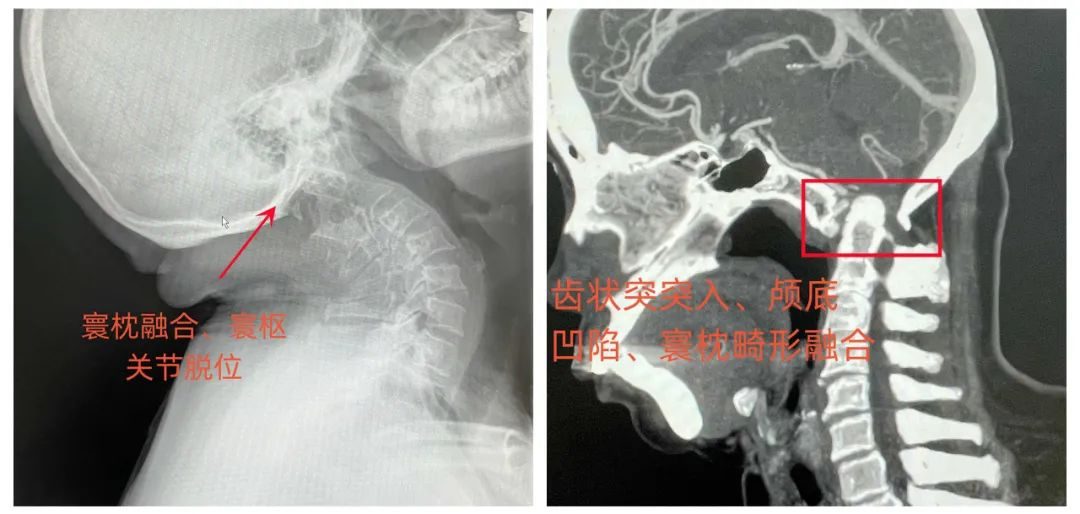

患者女性,63岁,不久前不慎摔伤,头部着地后当即颈项部疼痛,伴四肢麻木无力,随后到我院门诊脊柱外科就诊,入院时呈现不全瘫状态,四肢肌力差,左侧肢体肌力减退明显,双上肢感觉减退,无法正常行走,经常性头晕头痛,生活质量差。入院后经详细查体及影像学检查,发现该患者患有颅底凹陷症并颈脊髓缺血,寰枕先天性融合畸形、枢椎与颈3锥体先天性融合畸形、双侧额叶散在小缺血灶、右椎动脉先天性发育纤细,病情复杂。

▲术前X线及术前CT